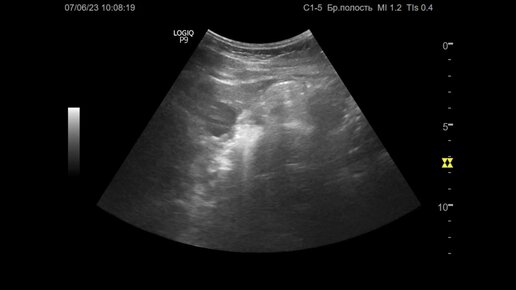

Ультразвуковая диагностика (УЗИ). Доктор Иогансен. Видеопримеры. Выпуск 31. Кисты печени.